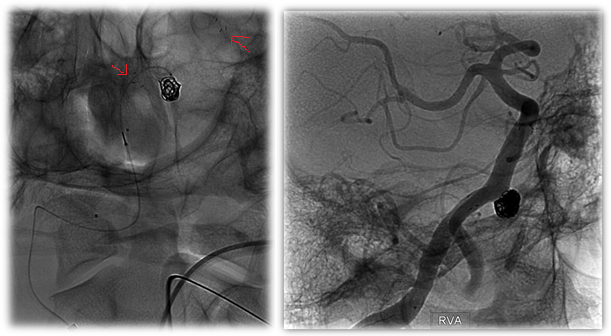

These very small stents are made of nitinol metal alloy that are cut by a laser in a specific pattern to optimize the contact with the blood vessel wall. Generally speaking, there are two design patterns to describe these types of devices, open-cell and closed-cell, and this refers to the configuration of the metal struts within the stent.

![]() Figure 4: Open-Cell Stent Design |

![]() Figure 5: Closed-cell stent Design |

Recently, Stryker Neurovascular developed a refined version of this type of stent called the Atlas Neuroform Stent System. This version of the stent uses a hybrid design that combines both types of cell arrangements to maximize the navigability and conformability of the stent while preserving the radial force needed to retain the coils. This device is special because for the first time it can be delivered through the same small microcatheter that is used to place the coils. Previously, larger catheters were required. Now, it is feasible to place the stent, and then use the same microcatheter to subsequently coil the aneurysm behind the stent. This advancement is non-trivial from a technology perspective, and has the potential to benefit patients with small, atraumatic access in a simpler, faster procedure.